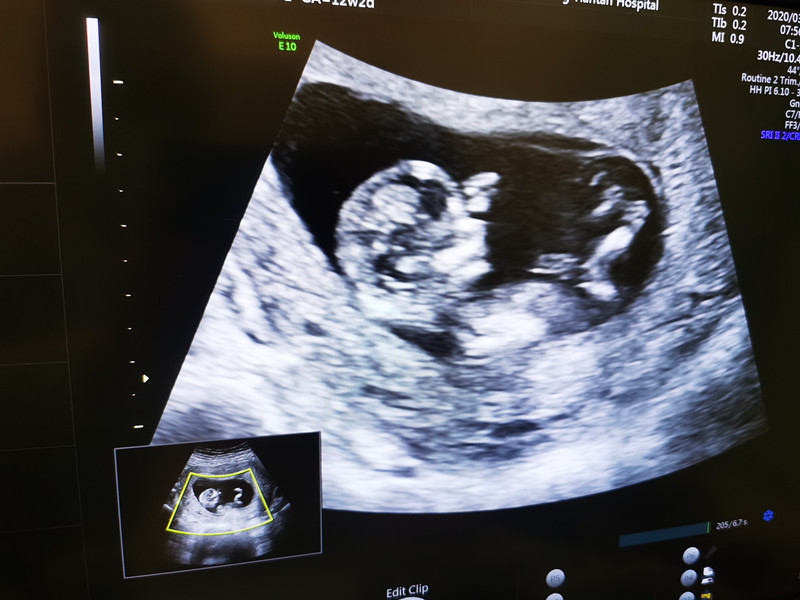

“你看,这是他的头,这是小手,还在动……”3月20日,是北京支援武汉医疗队在武汉工作的第54天,来自北京天坛医院的队员袁磊第一次通过B超影像,见到了自己的宝宝。

医院各级领导对支援武汉医疗队队员和家人的生活十分关心,特别安排护理部人文关怀小组组长苏娅丽等全程照顾。早上8点,杜晓彤在母亲的陪伴下来到北京天坛医院超声科,安静地躺在检查床上。随着超声科副主任医师王立淑的操作,显示屏上,一个小小的胎儿形象清晰地显示出来。

“袁磊,看看你们家宝宝,可爱吗?”苏娅丽用手机拍摄下显示屏上的画面,伸手、踢腿、翻身,这个87天的小生命似乎听到了外面的召唤,用各种动作回应大家的召唤,每一个动作都会引起大家的笑声。检查室里只有躺在床上的杜晓彤看不到屏幕,一脸茫然。

“今天是第一次看见他,他的小脑袋、小手、小脚,一直在动,特别活跃。我特别紧张,特别激动。在武汉这么多天,他一直就是我的牵挂,今天终于看到他,虽然还看不清他的样子,但是已经感受到他的活力。我觉得这是在武汉最好的礼物。”袁磊说。他叮嘱爱人:“照顾好自己,照顾好宝宝,好好吃饭好好睡觉,踏踏实实等我回家。”